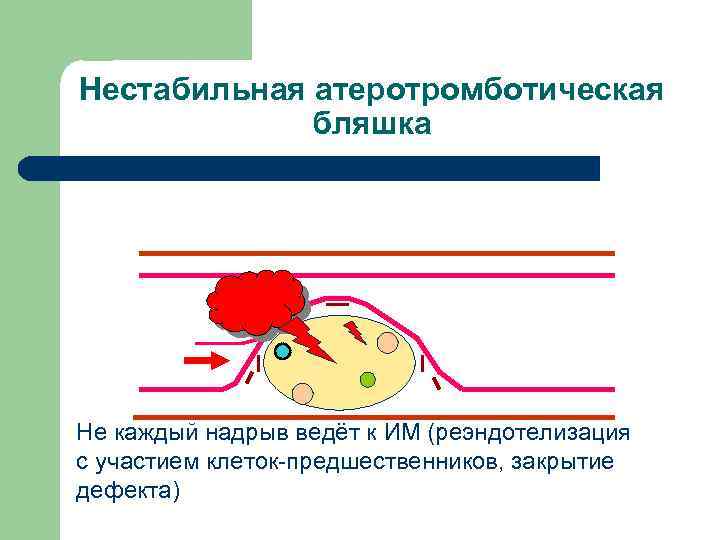

Нестабильная атеротромботическая бляшка Не каждый надрыв ведёт к ИМ (реэндотелизация с участием клеток-предшественников, закрытие дефекта)